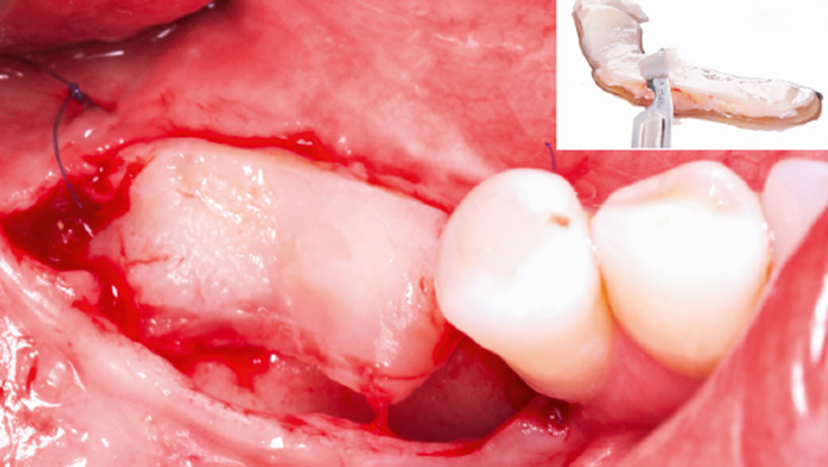

Na primeira fase, foi realizada uma cirurgia para enxertode tecido conjuntivo visando o ganho de espessura e o aumentoda faixa de mucosa queratinizada. Assim, o enxerto foi coletadoda região palatina e fixado com suturas simples (Microsuture).O período pós-operatório evoluiu sem intercorrências, com boaintegração tecidual após três meses (Figura 2).